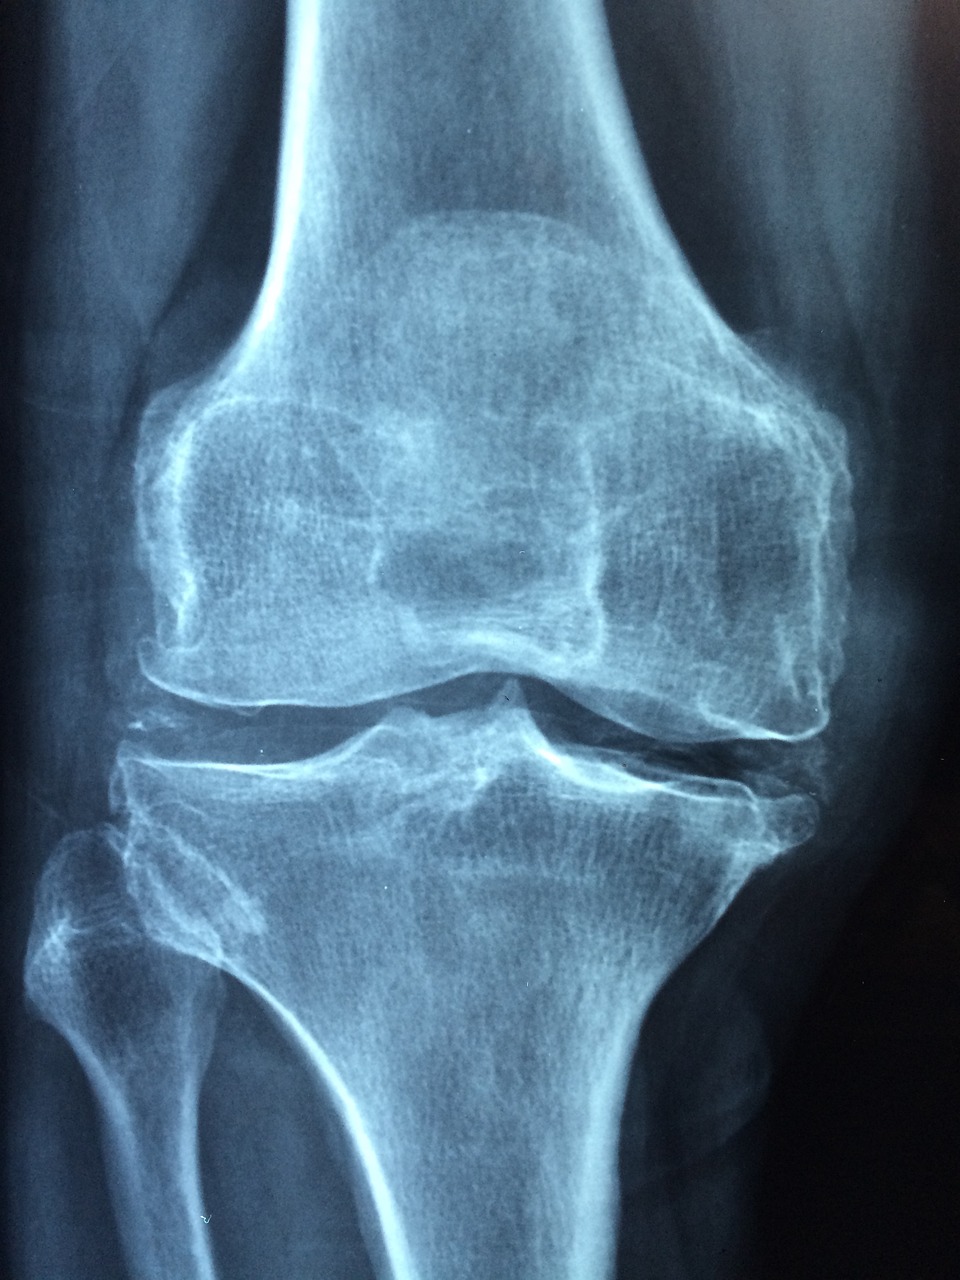

골다공증은 뼈의 강도가 시간이 지남에 따라 약해져서 쉽게 뼈가 부러지게 되는 골절이 발생하는 확률이 높은 상태를 말합니다.

골다공증이 발생하면 재골절의 위험도가 골다공증의 증상이 없는 경우에 비해서 상당히 높다고 나타나고 있기 때문에 미리 체크해야 합니다.